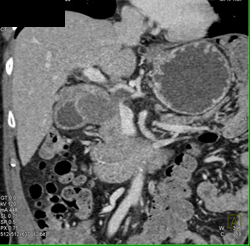

Pseudocyst